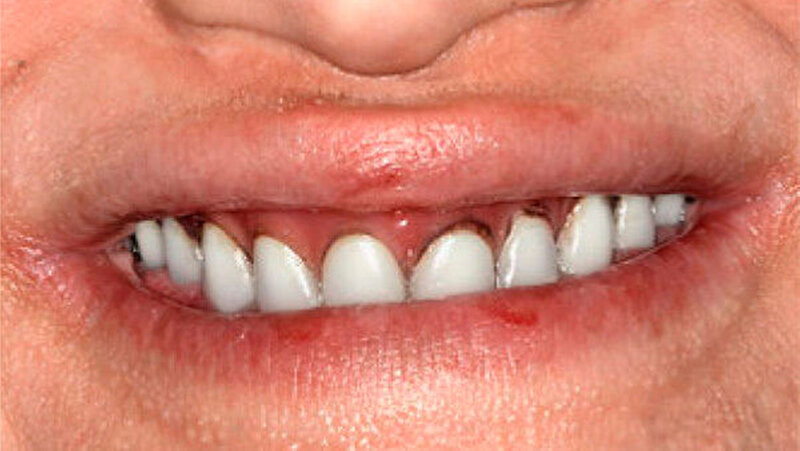

Die Patientin war mit einer knapp neunjährigen Teilprothese im Ober- und einer zweijährigen Totalprothese im Unterkiefer versorgt. Beim Lachen wurden die nicht mehr altersentsprechenden Prothesenzähne mit den deutlichen Randverfärbungen ersichtlich (Abb. 19). Das sagittale Wachstum des zahnlosen Unterkiefers führte in den letzten zwei Jahren aufgrund der verstärkten Kontakte im Frontzahnbereich zu einer beidseitigen Nonokklusion im Seitenzahnbereich (Abb. 20). Eine rasche Verbesserung der Ästhetik als auch der Funktion war unbedingt angezeigt, um das Selbstbewusstsein dieses puberalen Mädchens zu stärken.